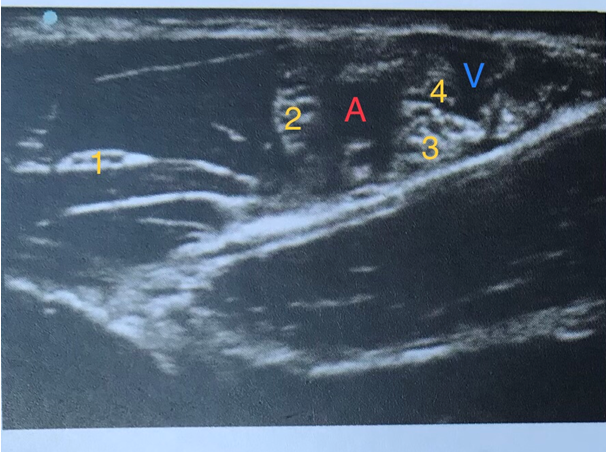

image

Décrivez les différents éléments anatomiques observés lors d'un bloc axillaire échoguidé (numérotés de 1 à 4).